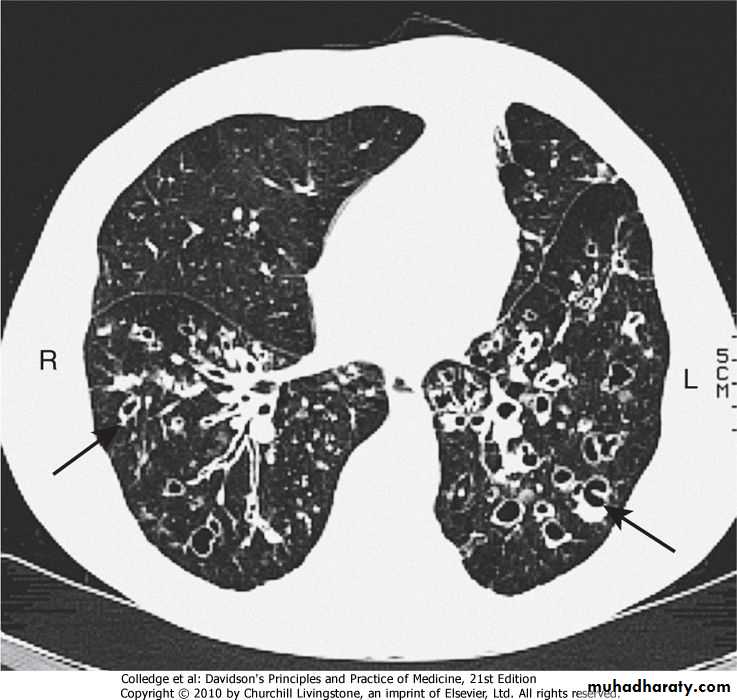

3-CT is much more sensitive, and shows thickened dilated airways

In advanced disease,cystic bronchiectatic spaces, pneumonic consolidation or collapse may be visible.